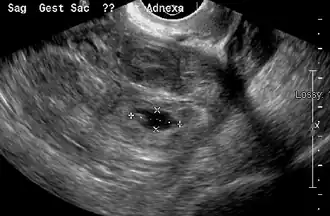

Transvaginal ultrasonography

An ultrasound showing a gestational sac with the fetal heart in the fallopian tube has a very high specificity for ectopic pregnancy. It involves a long, thin transducer, covered with the conducting gel and a plastic/latex sheath and inserted into the vagina.[38] Transvaginal ultrasonography has a sensitivity of at least 90% for ectopic pregnancy.[5] The diagnostic ultrasonographic finding in ectopic pregnancy is an adnexal mass that moves separately from the ovary. In around 60% of cases, it is an inhomogeneous or a noncystic adnexal mass, sometimes known as the "blob sign". It is generally spherical, but a more tubular appearance may be seen in the case of hematosalpinx. This sign has been estimated to have a sensitivity of 84% and a specificity of 99% in diagnosing ectopic pregnancy.[5] In the study estimating these values, the blob sign had a positive predictive value of 96% and a negative predictive value of 95%.[5] The visualization of an empty extrauterine gestational sac is sometimes known as the "bagel sign", and is present in around 20% of cases.[5] In another 20% of cases, there is visualization of a gestational sac containing a yolk sac or an embryo.[5] Ectopic pregnancies where there is visualization of cardiac activity are sometimes termed "viable ectopic".[5]

-

Transvaginal ultrasonography of an ectopic pregnancy, showing the field of view in the following image -

A "blob sign", which consists of the ectopic pregnancy. The ovary is distinguished from it by having follicles, whereof one is visible in the field. This patient had an intrauterine device (IUD) with progestogen, whose cross-section is visible in the field, leaving an ultrasound shadow distally to it. -

Ultrasound image showing an ectopic pregnancy where a gestational sac and fetus have been formed